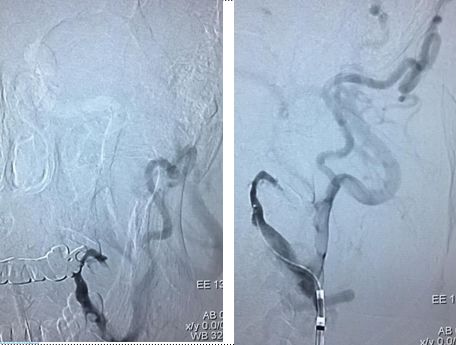

造影示:颈内动脉闭塞,眼动脉有代偿,血管闭塞原因决定血管再通方式!

找到闭塞血管部位,狭窄?夹层?

在颈内远端用6*30Solitaire逐次向近端释放支架(夹层可能性大)

支架释放状态血管通畅,逐渐找到血管闭塞部位